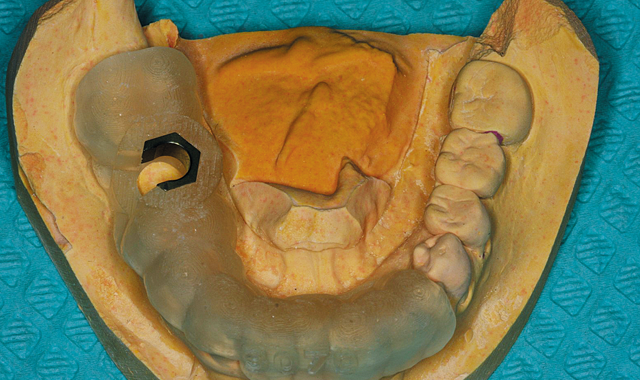

Fig. 6 Surgical guide to ensure predictable prosthetic results

From there, I can send the scans to a lab to merge the data files to make a surgical guide (Fig. 6). Both my CBCT and intraoral files are open-format (DICOM and STL, respectively), so I can send this information to the laboratory of my choice for fabrication. Merging CBCT and digital impressions is quickly streamlining dental implant surgery as well as improving accuracy of the results.3

Depending on what I see in the CBCT scan, I can order a surgical guide with pilot drills or a fully guided surgical guide that includes position, angle and depth. This is beneficial in a lot of ways, including having the ability to confidently perform the treatment plan as well as to obtain predictable results.